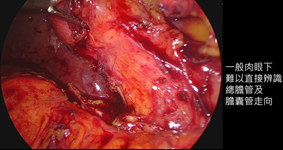

手術目前常見採微創方式處理,也就是「腹腔鏡膽囊切除術」,其優點是傷口較小,復原也較快。手術會採全身麻醉,以腹腔鏡將膽囊切除,若術前或術中懷疑有膽道結石,醫師會視狀況再做術中膽道攝影檢查。

在嚴重發炎的狀況下「ICG螢光顯影系統」可協助外科醫師分辨總膽管的位置